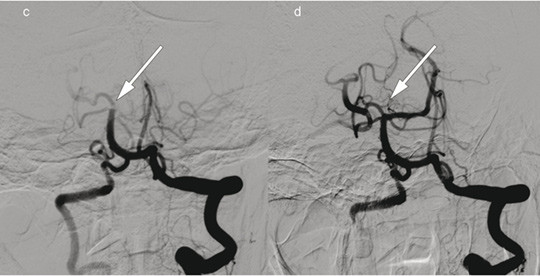

Patient 2. A woman in her 70s experienced acute onset of right-sided paralysis, dizziness and dysarthria after heart surgery. Her NIHSS score was 23 points (severe cerebral infarction). Intravenous thrombolytic therapy was contraindicated. The image to the right shows cerebral angiography with contrast injection in the left vertebral artery, c) before and d) after embolectomy of a large thrombus (arrows) with occlusion of the superior cerebellar artery, posterior cerebral artery and the bifurcation of the basilar artery. Embolectomy was performed with recanalisation 220 minutes after symptom onset. The event presumably occurred after heart surgery. Further workup also revealed atrial fibrillation. The patient received anticoagulation therapy with warfarin, and at follow-up three months later, the NIHSS score was 0 points.